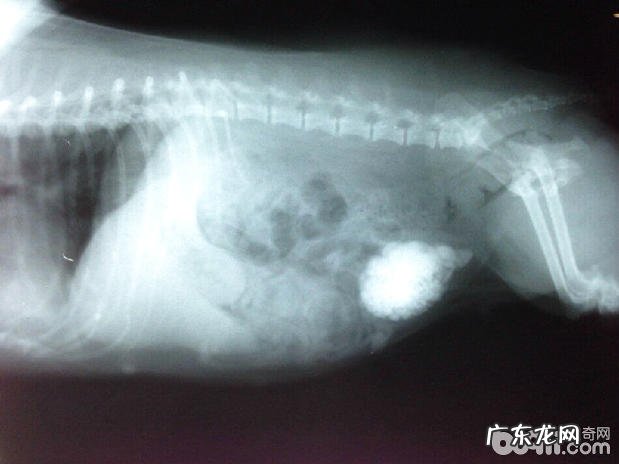

图1 犬尿道结石X射线检查

X射线检查关键做侧方和背腹位2个方向投照 , X射线指向直射位置定位点 。以背腹位观查为主导 。对患犬详尽纪录病症后 , 开展X线检查 。结石选用腹背位观查 , 一部分尿结石影象和椎间盘影象重合 , 细微尿结石非常容易轻视 , 观查时要细心鉴别 。侧方观查尿结石 , 常放置椎间盘正下方 , 居第二椎间盘与骨盆正中间位置 。背腹位观查膀胱结石 , 常坐落于坐骨结节的上边 , 横放置骨盆中心线位置 。背腹位和侧方都能够观查尿路结石 , 常见于公犬的尿道口弯折位置 。猜疑尿结石不可以诊断时 , 可以用泛影葡胺开展代谢性尿道口造影检查和逆向行驶尿道口造影检查 , 根据造影检查技术性开展辨别 。

3、 X射线检查